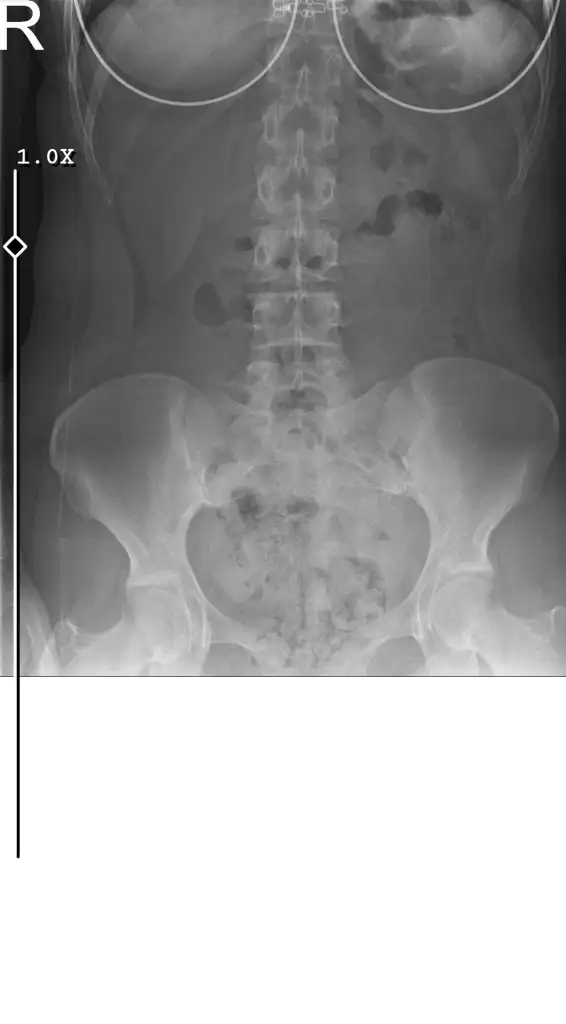

cok fazla gaz problemi yaşıyorum ayni durumda olan var mı ne yaptınız

• Röntgen.webp

11 KB · Görüntüleme: 1.931

Dün gece rahatsizlanip acile gittim. Karın filmi cektiler. Mideden çok bağırsakların dolu dolu dediler. Sanırım sindirim sorunu var. Genel cerrahi ya da gastroenteroloji ye yönlendiriyorlar. Onlar da muhtemelen kolonoskopi fln isterler. Evet şişlik oluyor. Arada balon patlar gibi minik sesler geliyor.